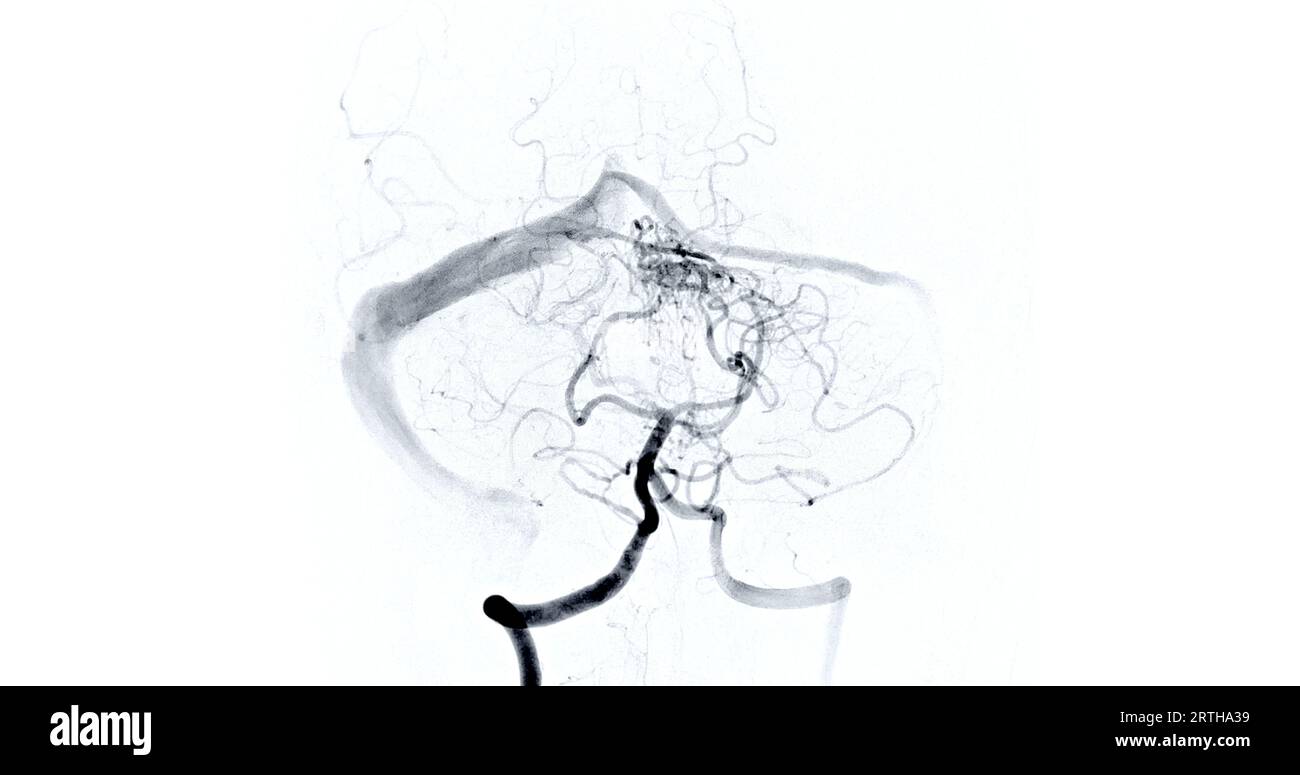

Fluoroscopy Intervention Radiology Image Revealing Cerebral Artery Fluoro Hysterogram The test may be done to look for the cause of. Check for a blocked fallopian tube. a hysterosalpingogram (hsg) is done to: a hysterosalpingogram (hsg) is a fluoroscopic examination of the uterus and the fallopian tubes, most commonly used in. a hysterosalpingogram is a diagnostic imaging modality primarily utilized in assessing female infertility. What is a. Fluoro Hysterogram.

Cerebral angiography image from Fluoroscopy in intervention radiology Fluoro Hysterogram a hysterosalpingogram is a diagnostic imaging modality primarily utilized in assessing female infertility. The test may be done to look for the cause of. hysterosalpingography (hsg) is an outpatient fluoroscopy procedure that evaluates the uterine cavity and fallopian. a hysterosalpingogram (hsg) is a fluoroscopic examination of the uterus and the fallopian tubes, most commonly used in. Check. Fluoro Hysterogram.

Cerebral angiography image from Fluoroscopy in intervention radiology Fluoro Hysterogram a hysterosalpingogram is a diagnostic imaging modality primarily utilized in assessing female infertility. a hysterosalpingogram (hsg) is done to: What is a hysterosalpingogram (hsg)? Check for a blocked fallopian tube. a hysterosalpingogram (hsg) is a fluoroscopic examination of the uterus and the fallopian tubes, most commonly used in. The test may be done to look for the. Fluoro Hysterogram.